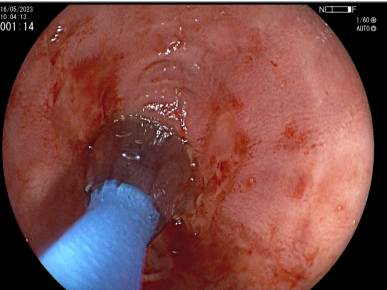

Extirpación de Tumores -

Mucosectomía

Extirpación de Tumores Incipientes

Esófago - Estómago - Cólon